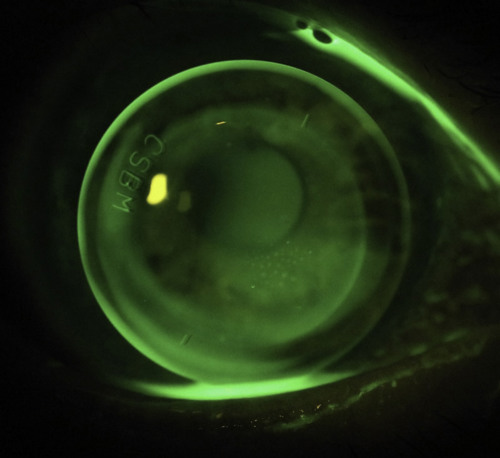

Her current right lens was providing acceptable vision of 6/10 with some cylinder in the over-refraction. On the eye, however, it was quite mobile and showed a fluorescein pattern typical of a spherical lens on a toric cornea. The edges were also very loose leading to excessive lid interaction (Fig 6).

Figure 6: My patient’s original, rotationally-symmetrical right lens. Note the steep central fit along the 70° meridian, the significant edge lift and the inferior nasal mislocation.

Using lens design software, I was able to design a toric back optic zone radius (BOZR) that closely matched the corneal shape with reverse geometry peripheral curves steeper than the BOZR, that allowed the lens to lock into place and make the lens more stable (Fig 7). At the patient’s most recent appointment she was ecstatic with the results. The lenses were no longer flicking out, were far more comfortable on the eye and achieved excellent 6/6 vision in each eye. She could now drive comfortably at night which she was reluctant to do with her previous lenses! Her left lens had a BOZR difference of 3.6mm between the two meridians which highlights how extreme some of these designs have to be to fit an irregular corneal graft.

Fig 7. My patient’s new right lens. As one of my colleagues eloquently puts it, inevitably RGPs on grafts still end up looking like a ‘dog’s breakfast’, however this lens has a much better central alignment and better peripheral fit than the original due to the toric reverse geometry design